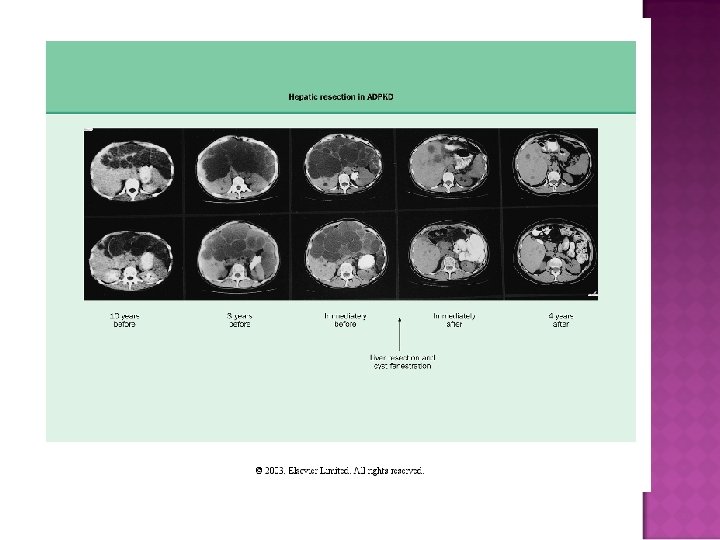

Easy diagnosis in overt disease: flank pain, positive family history, CRI, large kidneys with multiple bilateral cysts on CT or sonogram Cysts in liver, pancreas, and spleen What do you do with otherwise unexplained CRI, hematuria, with negative family history?